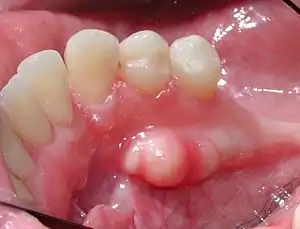

| Mandibular torus in premolar area | |